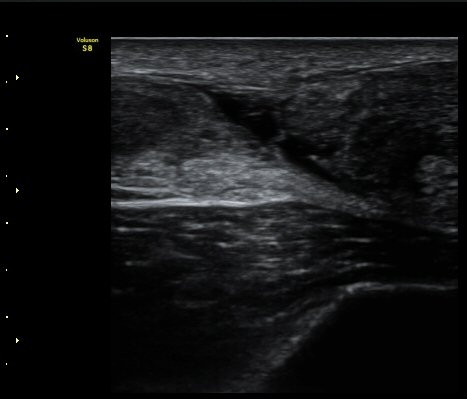

ÃÊÀ½ÆÄ °Ë»ç

d